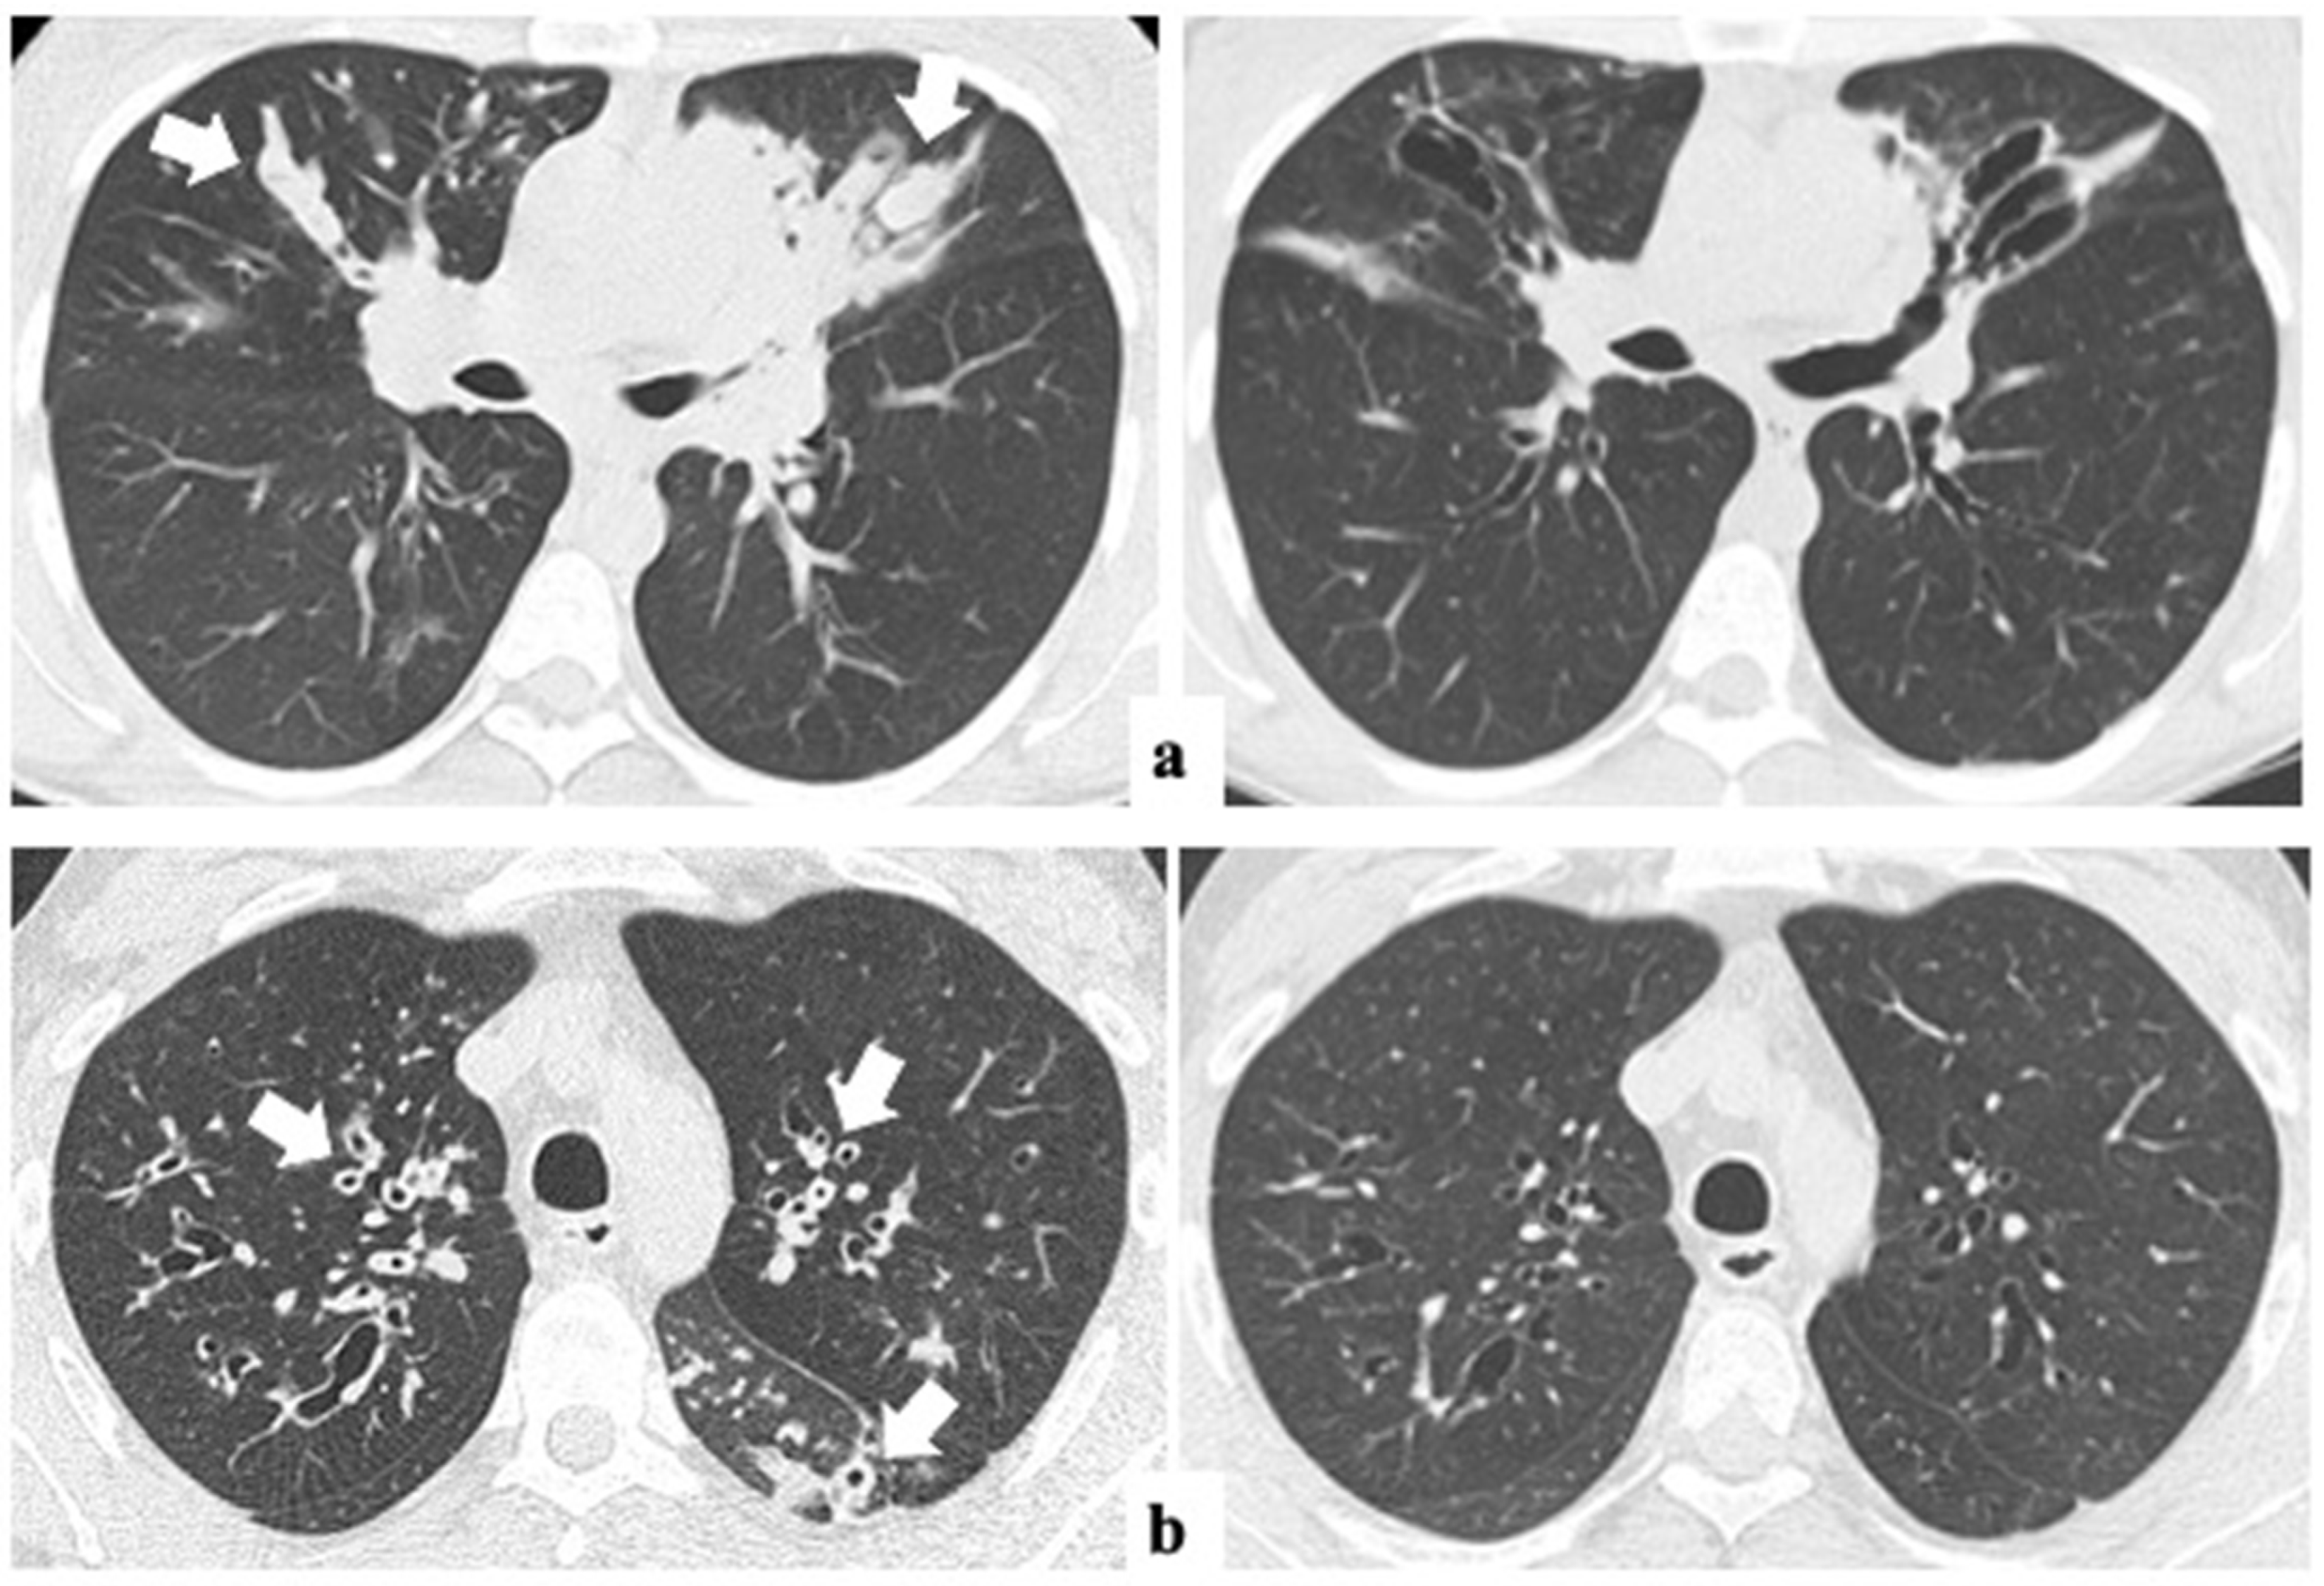

3.2. Changes in Radiology and Spirometry Parameters with ETI Treatment